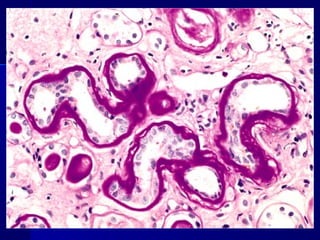

 NEFROPATÍA DIABÉTICA:NEFROPATÍA DIABÉTICA:

- Afectación glomerular da lugar a proteinuria progresi-- Afectación glomerular da lugar a proteinuria progresi-

va con IRC. Glomerolosclerosis nodular (lesiones deva con IRC. Glomerolosclerosis nodular (lesiones de

Kimmelstiel-Wilson)Kimmelstiel-Wilson)

Glomeruloesclerosis diabética

 MICORANGIOPATÍA DIABÉTICAMICORANGIOPATÍADIABÉTICA : engrosamiento: engrosamiento difuso de las membranas basales de las arterias peque-difuso de las membranas basales de las arterias peque- ñas y de los capilares (evidente en piel, retina, músculoñas y de los capilares (evidente en piel, retina, músculo esquelético). También afecta a túbulos renales, cápsulaesquelético). También afecta a túbulos renales, cápsula de Bowman, nervios periféricos.de Bowman, nervios periféricos.  NEFROPATÍA DIABÉTICA:NEFROPATÍA DIABÉTICA: - Afectación glomerular da lugar a proteinuria progresi-- Afectación glomerular da lugar a proteinuria progresi- va con IRC. Glomerolosclerosis nodular (lesiones deva con IRC. Glomerolosclerosis nodular (lesiones de Kimmelstiel-Wilson)Kimmelstiel-Wilson) - Vascular: arteriosclerosis- Vascular: arteriosclerosis - Infección: ITU, con pielonefritis.- Infección: ITU, con pielonefritis.